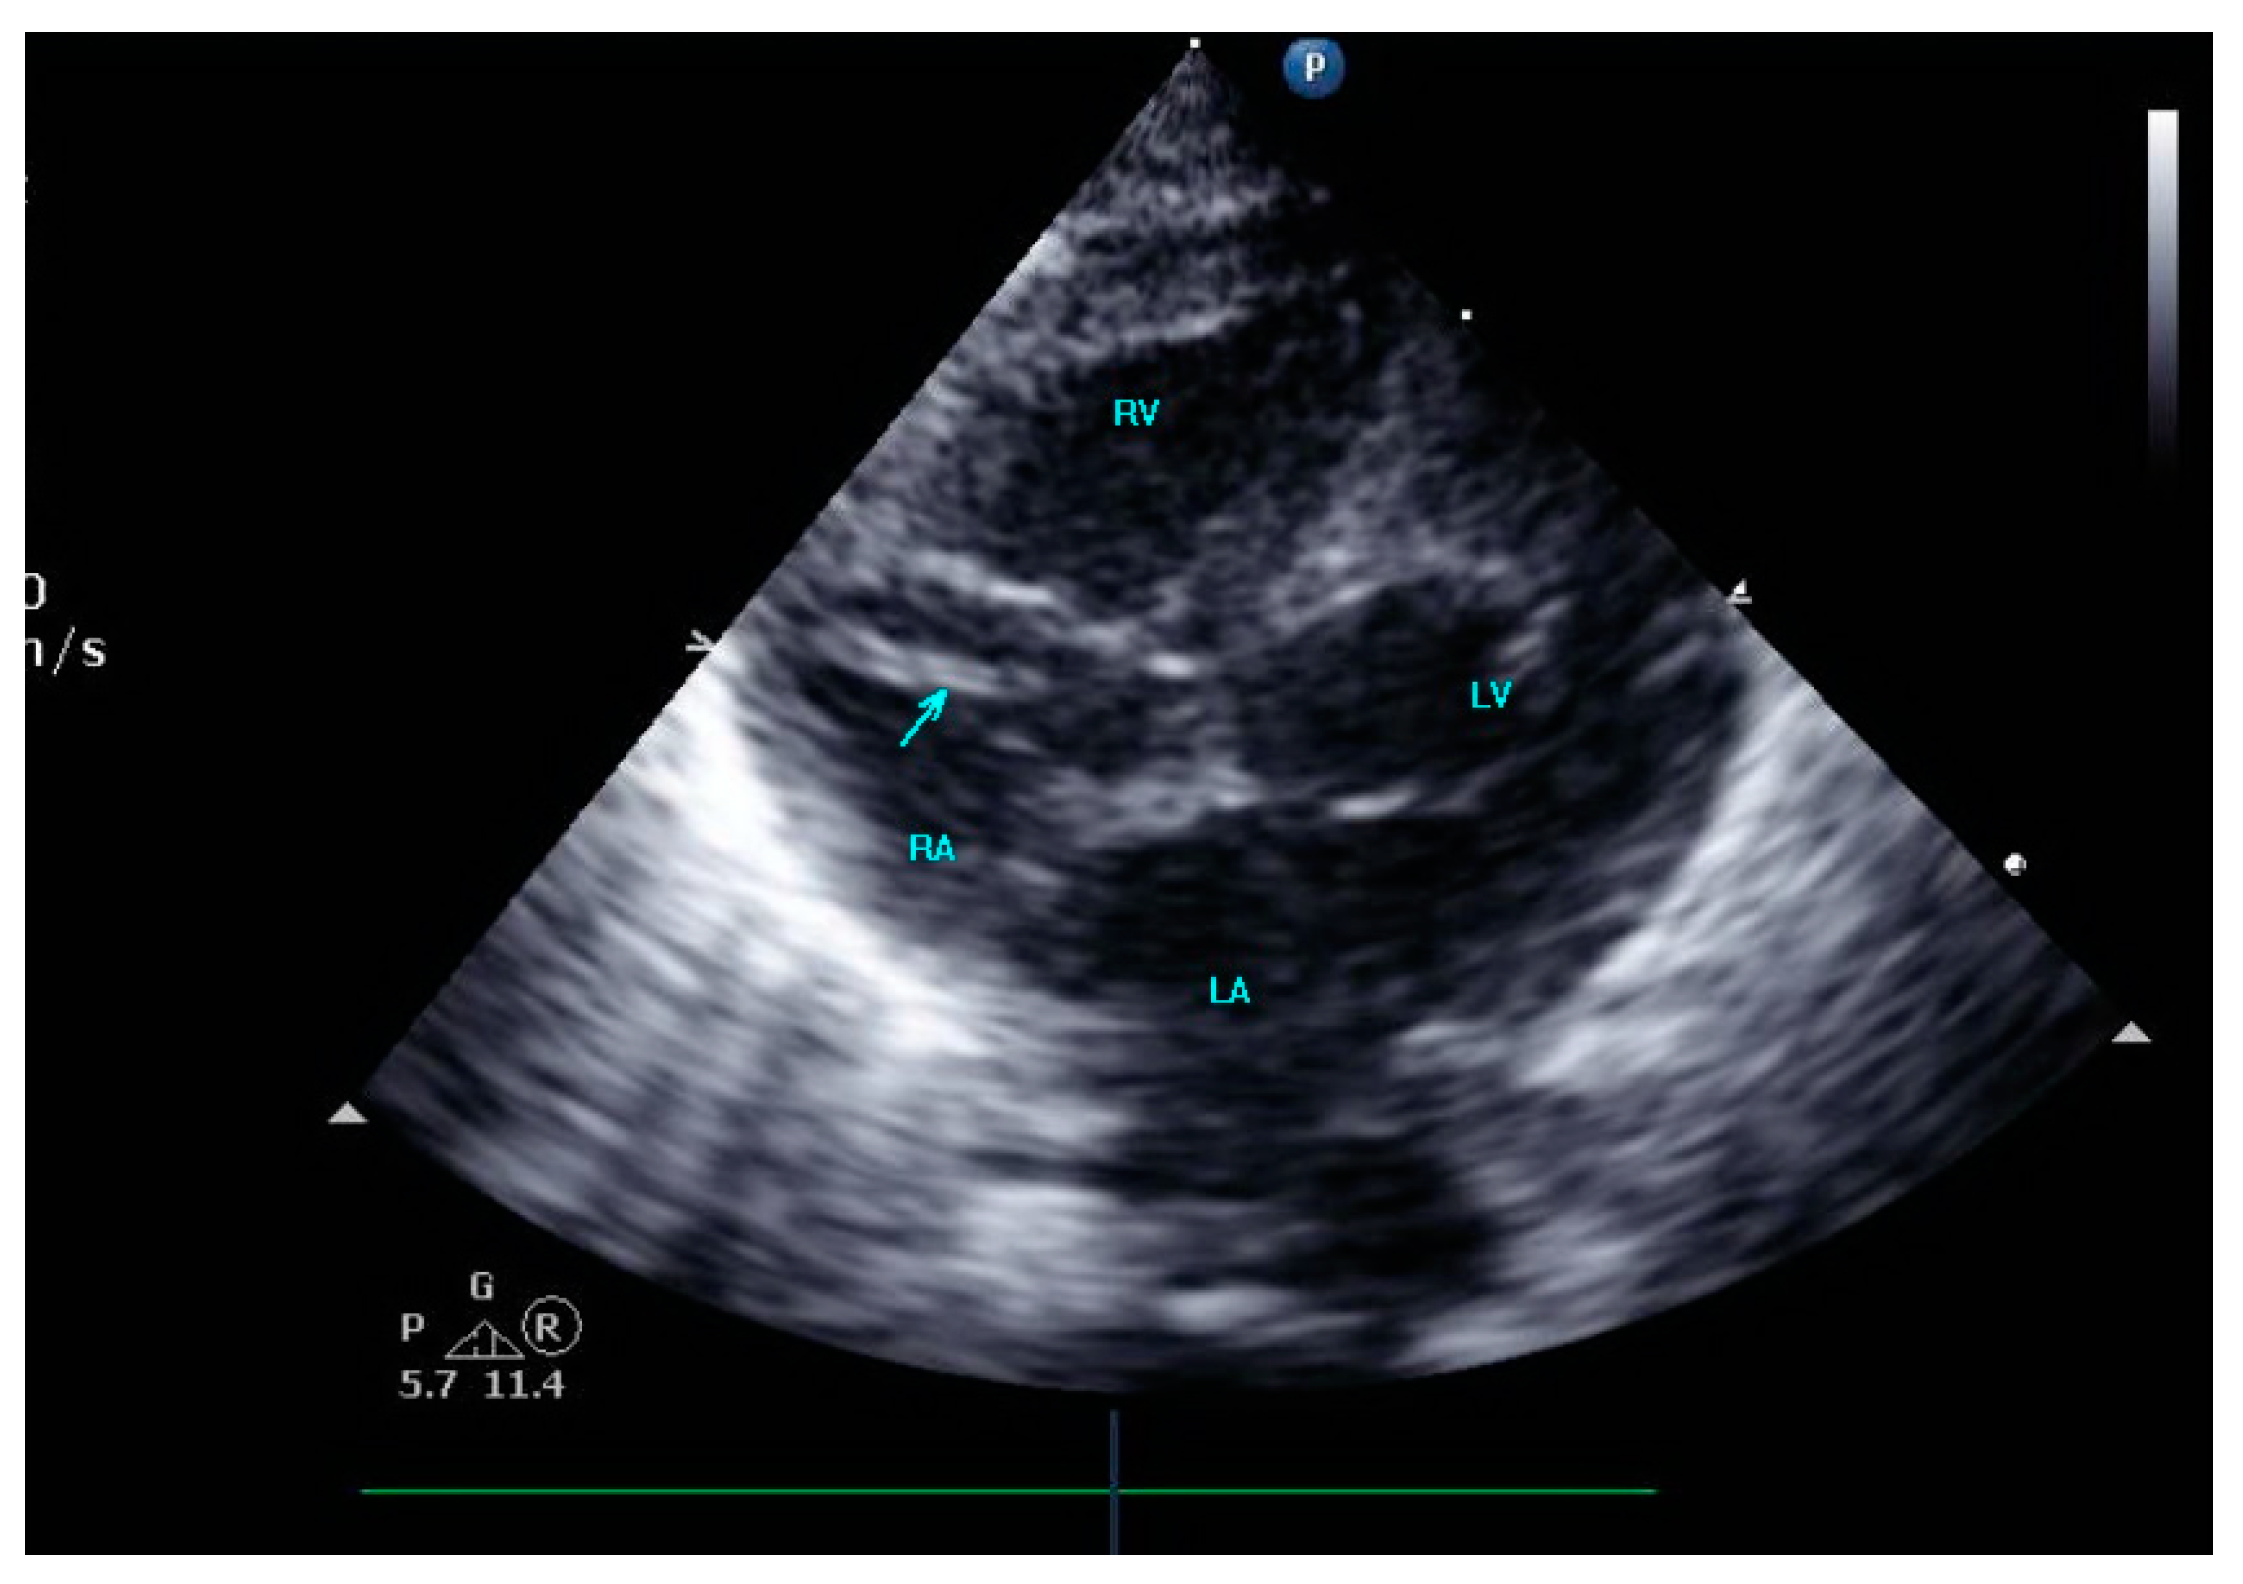

2. Case Presentation

3.5. Echocardiographic Diagnostic Features of Intracardiac Thrombi